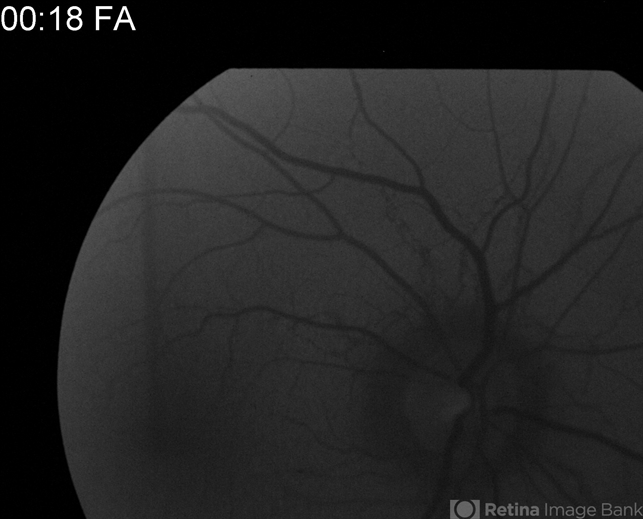

- angioid streaks

- Charlotte Harris Midwest Eye Institute Indianapolis, IN

Fundus camera

TOPCON EX - Description

- FA of a 24-year-old male with mild onset of blurry vision, angioid streaks OS>OD. Observation recommended for now.